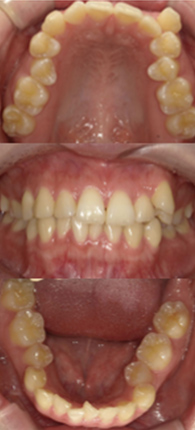

症例紹介

症例1

八重歯きれいにして前歯のガタつきを治したいとご来院された女性の症例です。

抜歯をして、1年半で完了しました。

約1年半後

ホワイトニング併用

| 治療費用 | 矯正検査代 33,000円、基本治療費 990,000円、調整料 5,500円×18回、 保定装置 55,000円、ホワイトニング剤 6,600円 |

| 治療のリスクについて | ホワイトニングでは歯がしみることがありますが、当院では知覚過敏予防の歯磨剤をお渡しし、症状の軽減に努めています。また、矯正治療においては歯肉退縮のリスクがありますが、丁寧な歯磨き指導を行うことで予防に取り組んでいます。 |